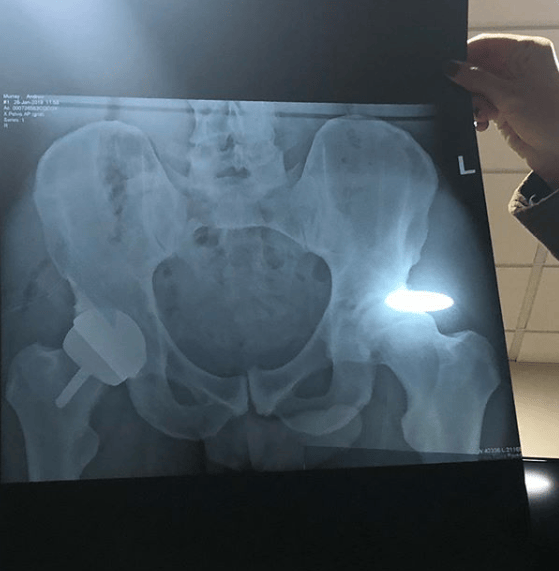

After his hip surgery Andy Murray shared a picture of himself in the hospital and a picture of his Xray showing his metal hip. Seventeen months after undergoing a career-saving hip surgery Andy Murray is starting to see the benefits as he finally able to serve well again. Andy Murray underwent hip surgery this past winter and now many people are wondering whether or not he can return to the tennis court. ANDY MURRAY has made an emotional return to Wimbledon after undergoing two hip operations.

But people on social media spotted something else in his X-ray. He then missed all the remaining championships in 2019 following his surgery. Jack Harkness and Miller Thomson join 77. A padel tennis company backed by Andy Murray is to open three courts at one of Londons biggest shopping centres.

In the Xray everyone was able to see the shadow of his penis. Murray is set to play his first singles tournament at a grand slam since having a metal plate inserted into his joint in January 2019 when he takes to the Arthur Ashe court at the US Open on Tuesday to play Yoshihito Nishioka. Britains Andy Murray has had hip surgery in Melbourne and. Andy Murray is pictured after undergoing hip surgery andymurray Instagram Speaking before he left Melbourne two weeks ago Murray explained how much the operation.